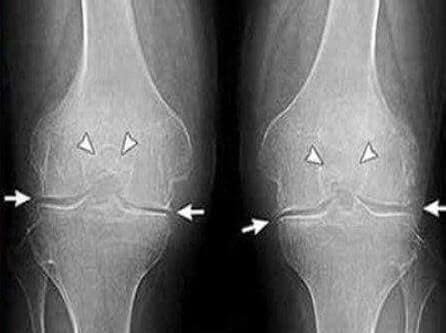

35 кун: таҳлил топширдим ва рентген қилдирдим. Артроздан ҳеч қандай из ҳам қолмаган! Бўғимлар тўқималари ҳудди 30 ёшдаги йигитдек. Шифокор ўтган сафарги рентгенда камчилик ёки тушунмовчилик бўлгани сабабли, артроз ташхиси хато бўлган бўлиши мумкинлигини айтди.

Соғлиғим тўғри келмагани учун оғир атлетика бўйича спорт устасиликдан кетдим. Шуғулланганлар мени тушунишади, кўпгина мусобақалардан кейин буткул «тамом бўлган» ҳолда бўлардим. Бундан кейин қурилишда ишлардим, ҳуллас, бўғимлар худди 70 ёшли одамникидек эди. Шифокор менга OSTEO9.19 ни тавсия қилди, ўқиб чиқишим бўйича, изоҳлар ёмон эмас эди. Сотиб олдим ва даволандим. Ва ҳақиқатдан ҳам, бўғимлар ўз холига қайтди! Қайта рентгенга тушдим – деярли барча ттўқималар бутунлай тикланганди. Албатта, катта спортга энди қайтмайман, лекин машғулотларга жоним билан қатнашаяпман, ўзимни буткул соғлом ҳис қилаяпман.